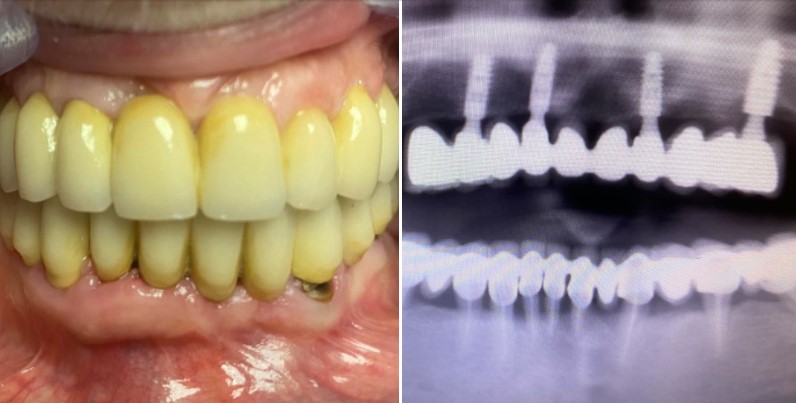

Lo studio dentistico del dr. Michele Piombino a Caserta offre la gamma più completa di servizi e specializzazioni in ambito odontoiatrico grazie alla pluriennale esperienza e all'impiego dei sistemi più evoluti e riconosciuti scientificamente a livello internazionale. Lo Studio Piombino offre ai propri pazienti trattamenti altamente specializzati e ad altissima affidabilità di implantologia osteointegrata, protesi estetiche e riabilitazioni totali fisse, anche nei grandi riassorbimenti ossei, proponendo trattamenti all inclusive immediati, quali ONE-DAY-TEETH, SYNCONE ALL-ON-FOUR, carico immediato impianti post-estrattivi. Presso lo studio Piombino è, inoltre, possibile eseguire trattamenti ortodontici fissi, mobili ed invisibili per la cura delle malocclusioni dento-scheletriche. Convenzionato con Previmedical, RSDA, Blue Assistance, Odontosalute, Odontonetwork.